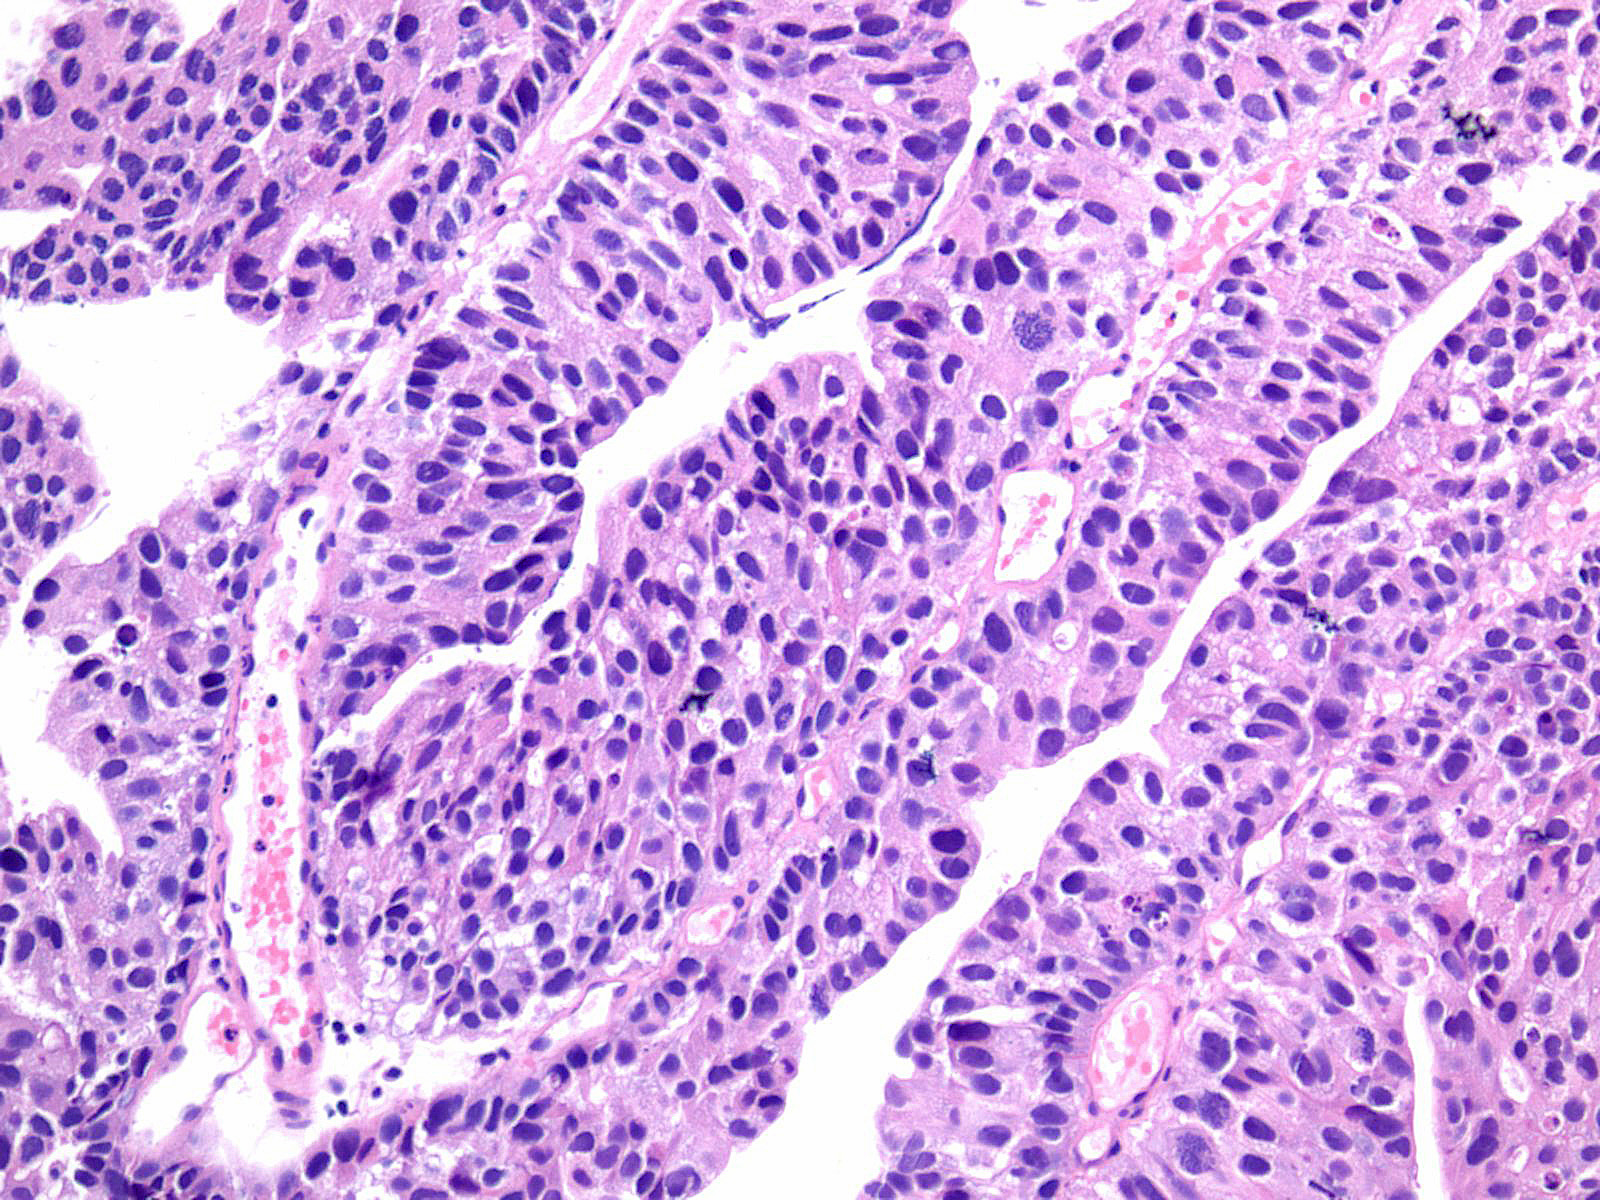

Consensus grade: High-grade papillary urothelial carcinoma (HG-PUC)

Lesion shows marked variation in nuclear size, shape and chromatin. Architecturally, cells appear irregularly clustered and the epithelium is disorganized. Mitotic figures are frequently seen at all levels.